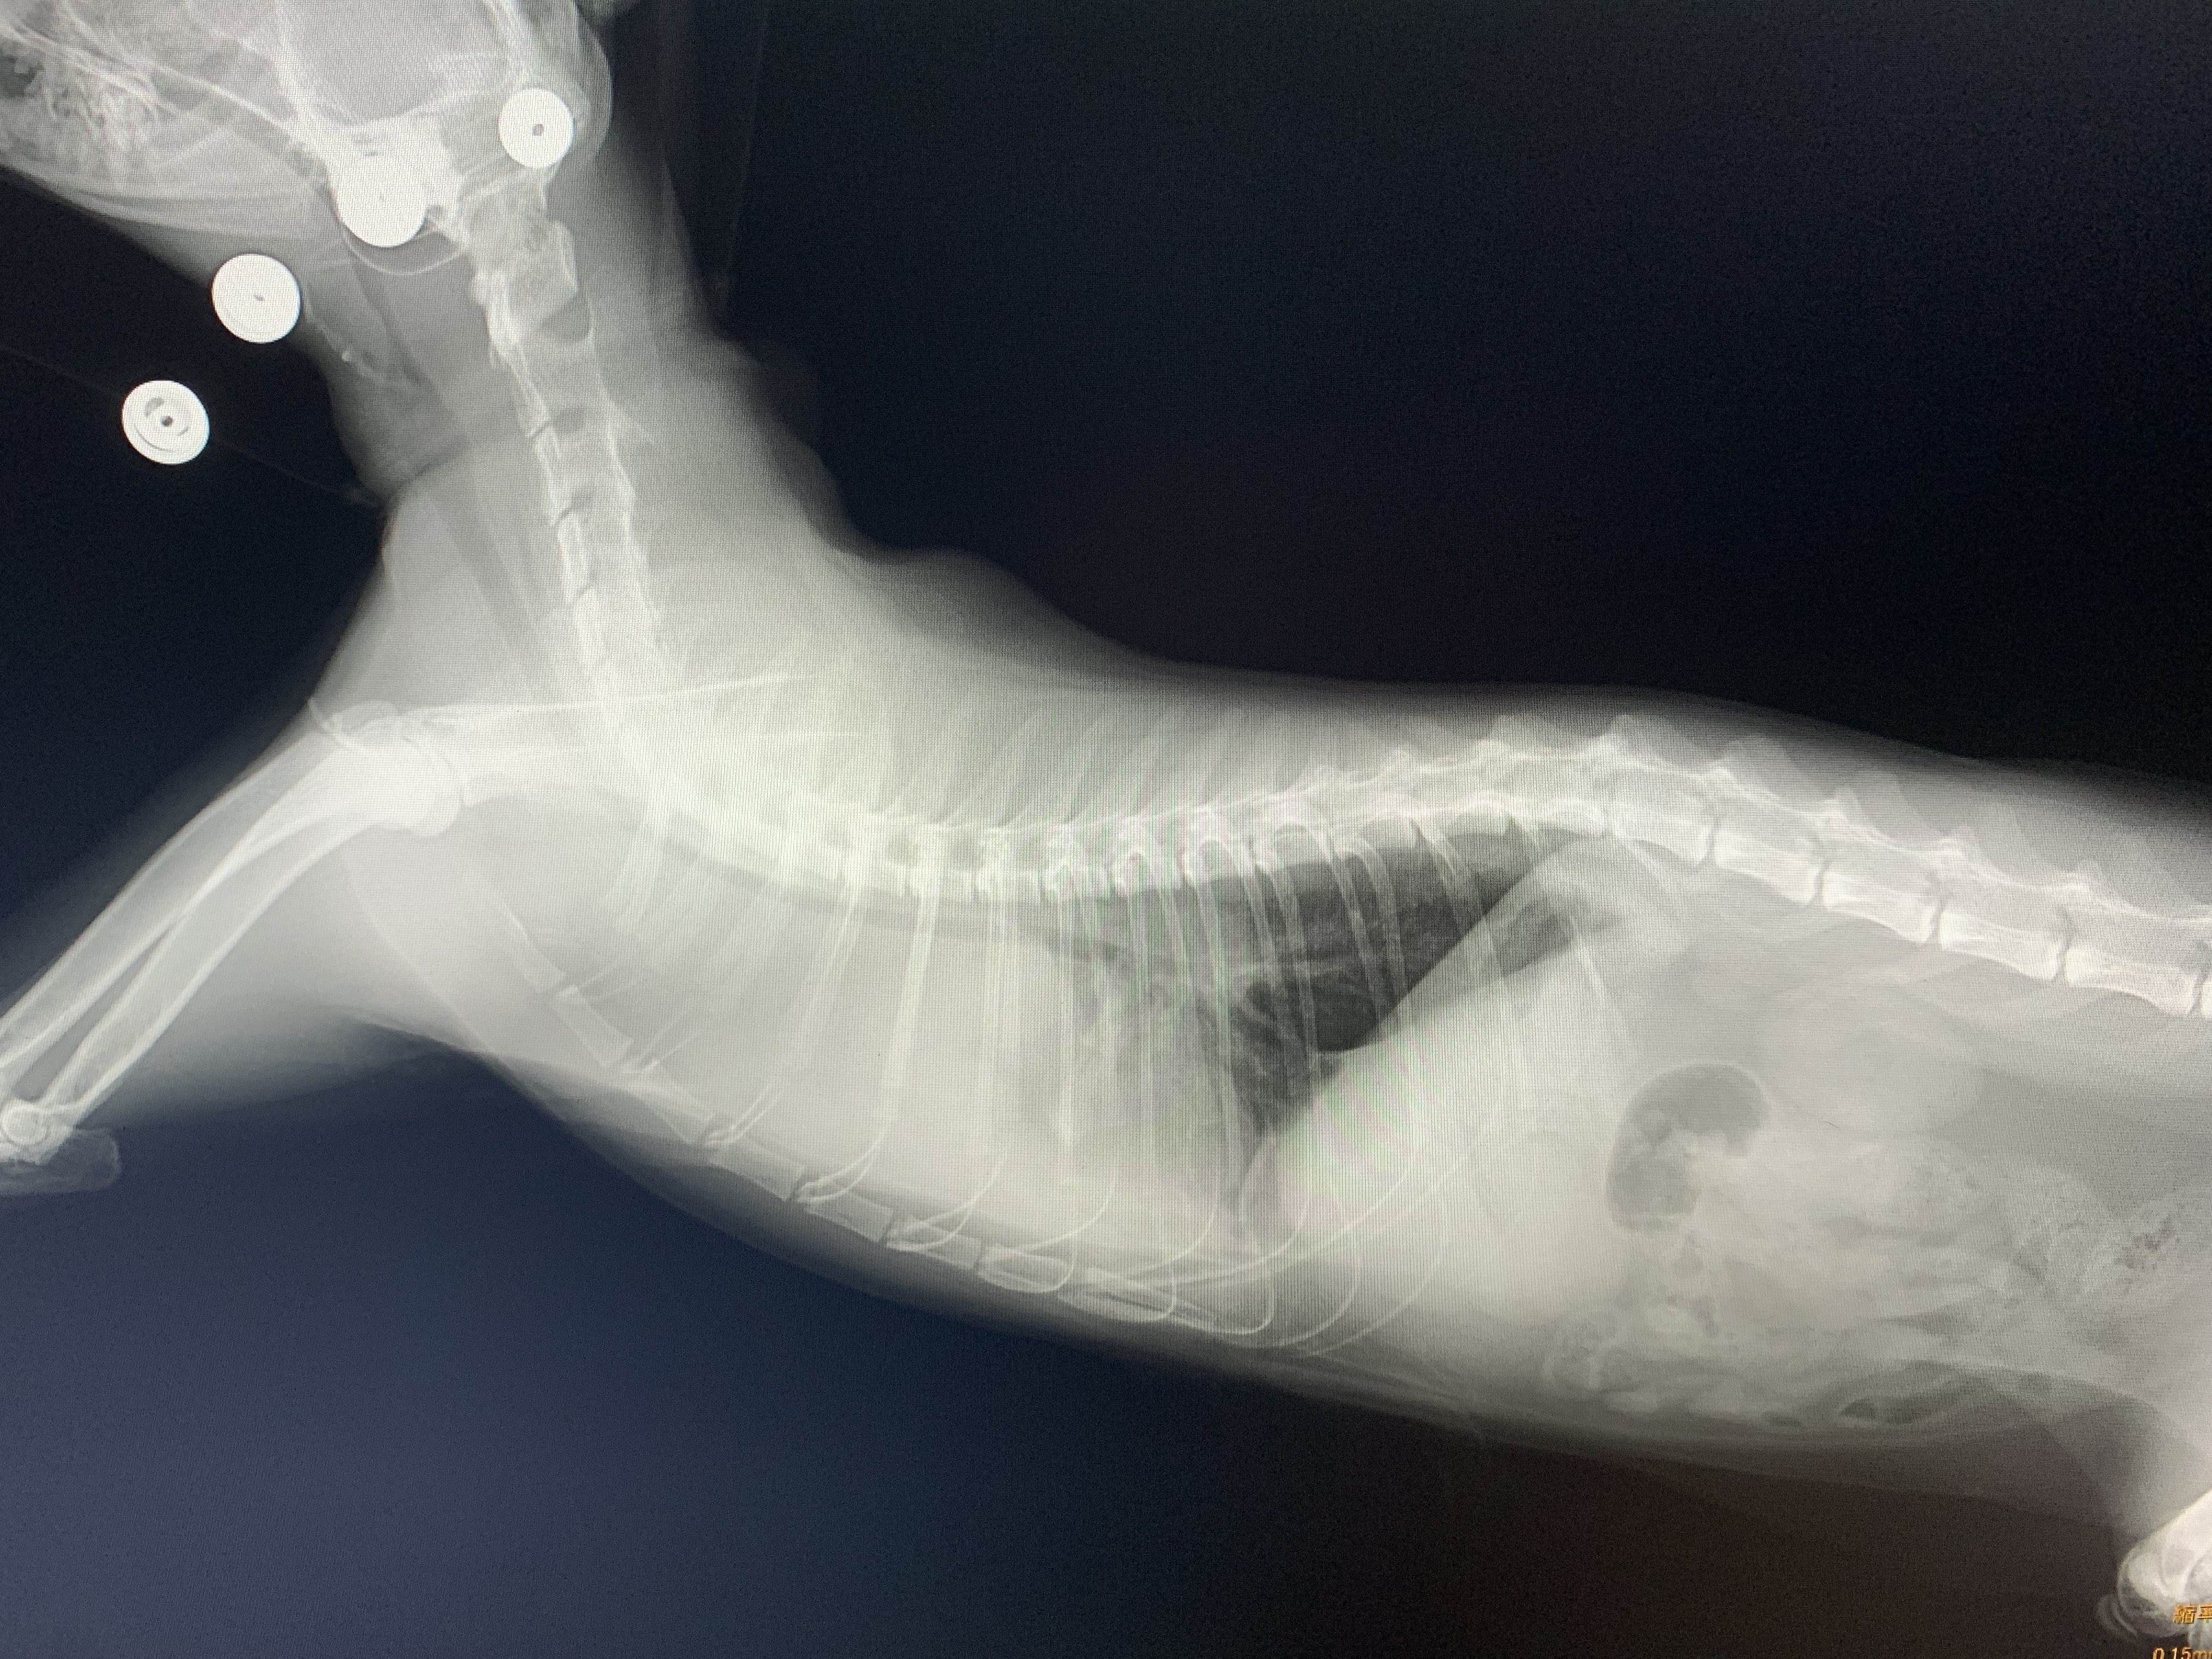

5. 呼吸困難:リンパ腫が呼吸器系に影響を与えることがあります。特に猫ウイルス性白血病に罹患した猫は、胸腺型リンパ腫を発生しやすく、胸の中に塊ができたり、胸水が溜まったりして、呼吸困難からリンパ腫であることがわかることがあります。